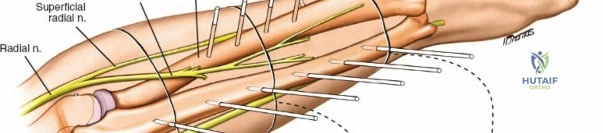

Radius Safe Zones

* Middle Third: Pins can be placed dorsolaterally. The superficial radial nerve (SRN) and cephalic vein must be protected.

* Distal Third: The SRN emerges from beneath the brachioradialis approximately 9 cm proximal to the radial styloid. Pins are typically placed at a 45-degree angle between the extensor carpi radialis longus (ECRL) and brachioradialis, or directly laterally. A mini-open approach is critical here.

Radius External Fixation

External fixation of the radial diaphysis requires meticulous attention to the superficial radial nerve and the posterior interosseous nerve.

Distal Radius Pin Placement

1. Identify the interval between the brachioradialis and the ECRL.

2. Make a 2-3 cm longitudinal incision.

3. Carefully identify and retract the superficial radial nerve branches.

4. Place the drill sleeve directly on the radial styloid or slightly proximal, aiming ulnarward and slightly dorsally.

5. Insert 3.0 mm or 4.0 mm pins.

Neurovascular complications, while less common, carry significant morbidity. The radial nerve is at highest risk during humeral fixation, while the superficial radial nerve is frequently irritated or injured during distal radius fixation. Adherence to the mini-open technique, utilizing blunt dissection to the periosteum, is the standard of care to mitigate this risk.